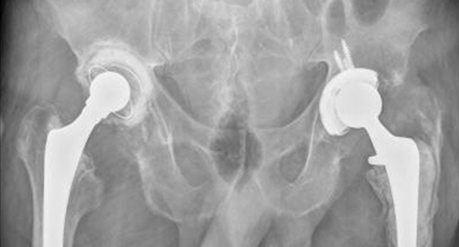

Tratamiento de la coxartrosis?

A

Terapia fisica

Corticoesteroides

AINES

Artroplastia ( Total vs hemi)